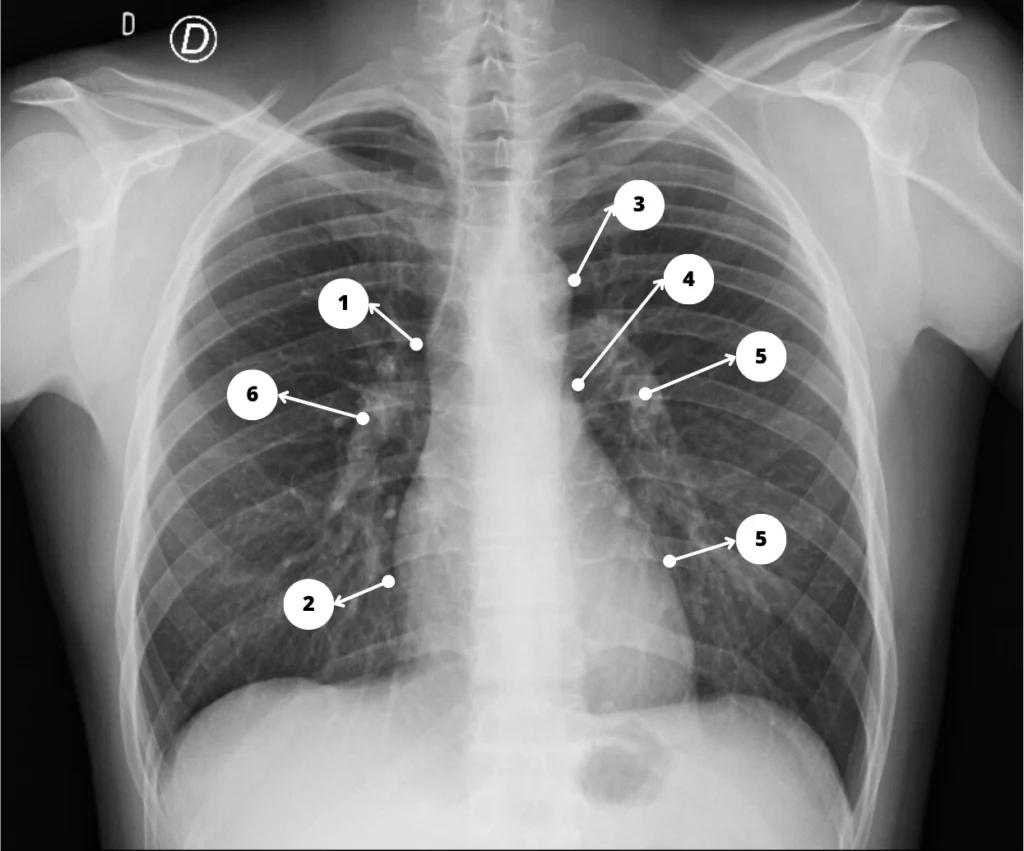

Radiografía de tórax

- ABCDEF — Post de mnemotecnia (publicado): “Informe de la radiografía de tórax: Mnemotecnia ABCDEF”.

- Guía aplicada (publicada): “Cómo interpretar una radiografía de tórax”.